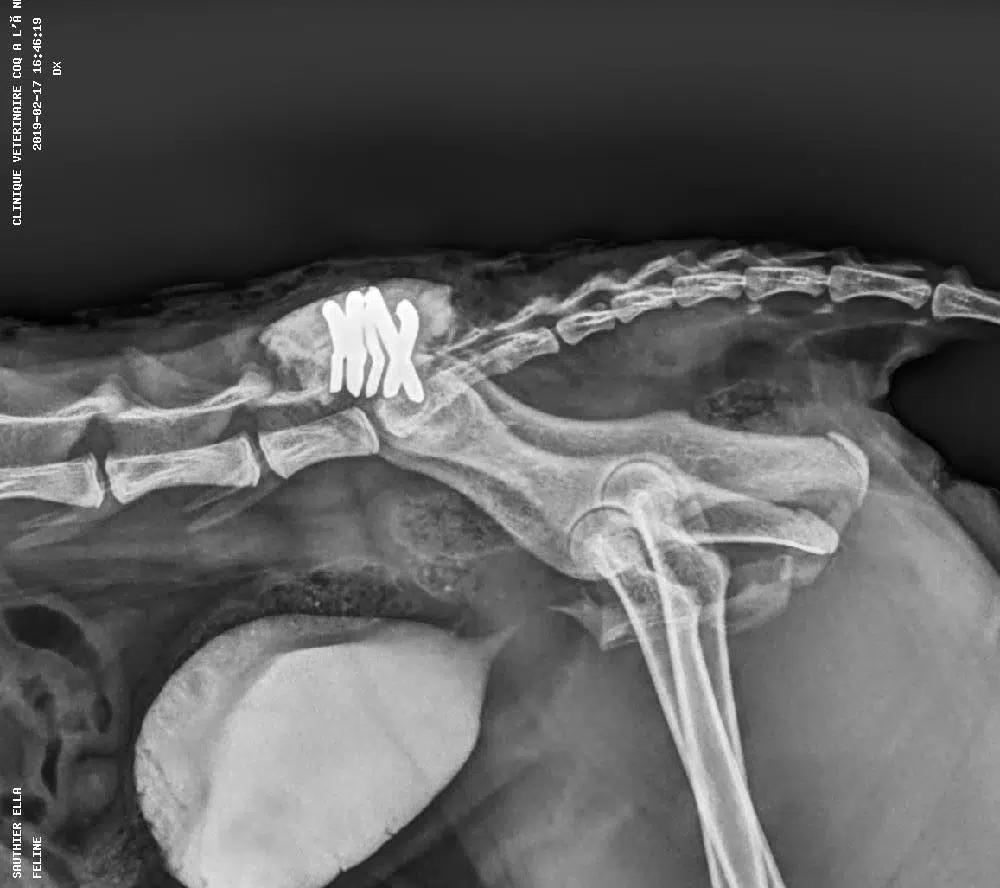

• Une radiographie numérique avec un système capteur plan